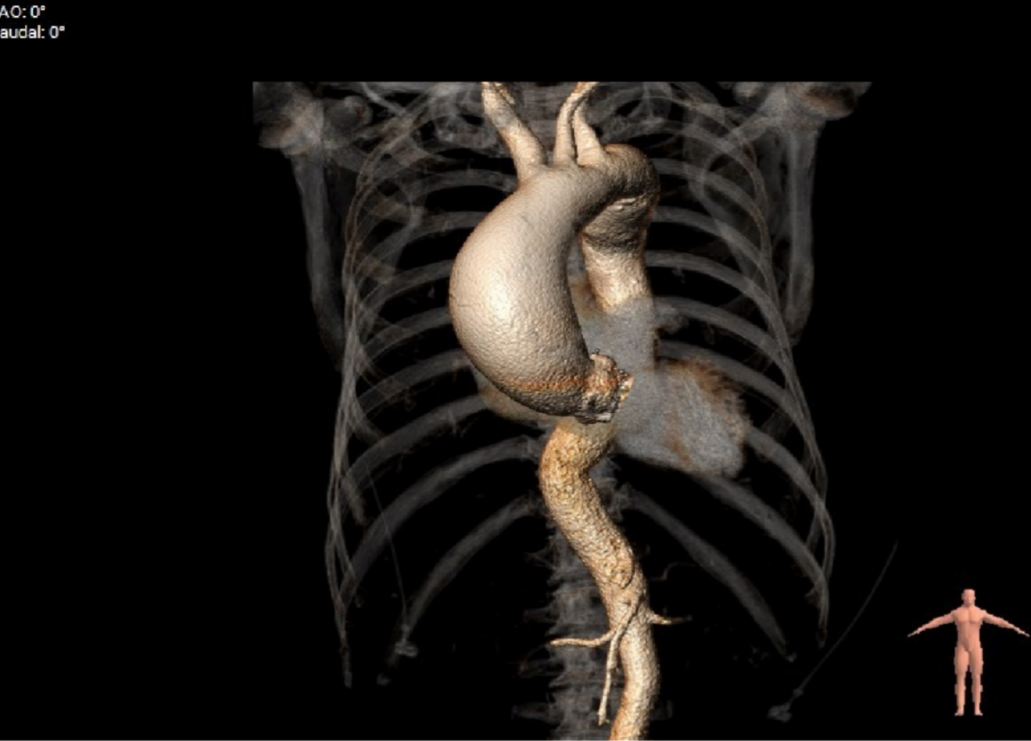

患者为79岁老年男性,因“劳力后胸闷气短5年,加重1周”入院。此次来海军军医大学第二附属医院心内科就诊,心脏超声提示:主动脉重度狭窄伴中度关闭不全;全心增大,左室肥厚;升主动脉瘤样扩张;LVEF:53%。遂以“主动脉狭窄(重度)”收治入院。

升主动脉最大直径66.5mm。

主动脉弓角度与宽度可,心脏水平夹角68°,横位心。

入路血管存在较大迂曲,双侧血管内径良好,主动脉弓部夹角及弓距尚可。

该患者为一例合并升主动脉瘤的大角度横位心重度AS患者。

3. 升主动脉扩张明显,合并大角度横位心,器械进入走行时存在一定困难,须注意防范血管并发症风险;